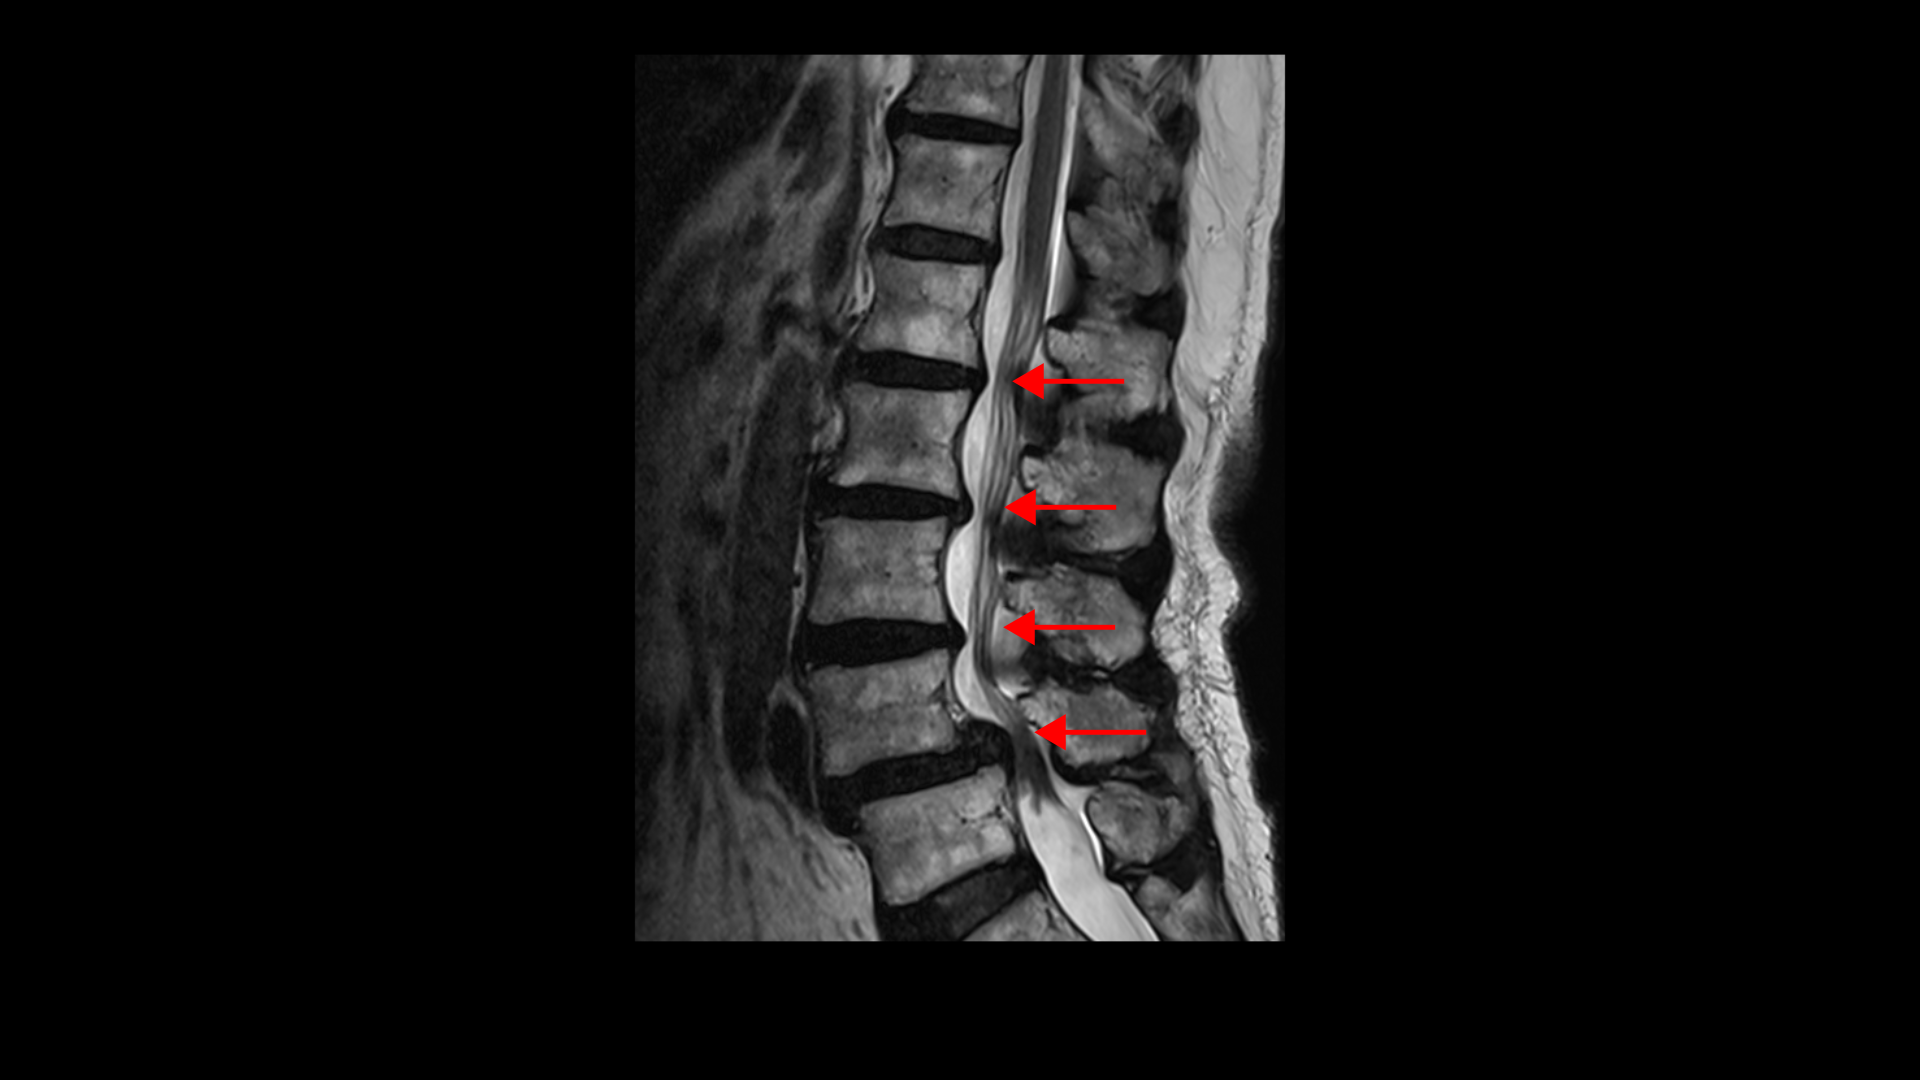

이 환자분 상태를 먼저 설명 드린 후 이분 말씀을 들어보겠습니다. 이분은 협착증을 앓으신 지 약 7년 정도 되셨습니다. MRI를 보면 여러 마디에 퇴행성 디스크가 있고

4번, 5번에는 전방전위증이 있습니다.

전방전위증이 있는 4번, 5번 마디에서는 오른쪽, 왼쪽 신경가지가 나가는 양쪽 추간공이 모두 좁아져 있고

그리고 척추관도 황색인대가 심하게 두꺼워지면서 중심성 협착도 매우 심합니다.

이 환자분의 근육을 MRI에서 보면 5번, 1번 마디에서 기립근과 장요근을 체크해봤을 때 기립근의 지방화 정도도 심하고 장요근, 특히 왼쪽 장요근은 거의 형체를 알아보기 어려울 정도로 위축이 심한 상태입니다.